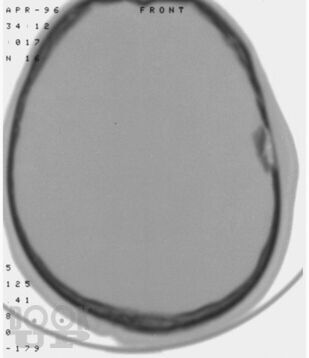

Учебное пособие написано в соответствии с основной профессиональной образовательной программой — программой подготовки кадров высшей квалификации в ординатуре по специальности 31.08.56 «Нейрохирургия». Издание содержит 144 ситуационные задачи. В задачах приводятся клинические случаи по всем разделам программы, в том числе рассматриваемые на смежных с нейрохирургией дисциплинах. Особое внимание уделено клиническим примерам, иллюстрирующим основные неотложные состояния у пациентов и раненых нейрохирургического профиля.

Ситуационные задачи составлены с целью обучения ординаторов методике диагностики травм и заболеваний нервной системы; также они могут быть актуальными и для практикующих нейрохирургов в качестве справочного пособия, в котором приведены алгоритмы диагностики и стандарты оказания помощи при наиболее распространенных нейрохирургических заболеваниях и травмах.